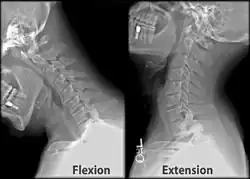

Function

The movement of nodding the head takes place predominantly through flexion and extension at the atlanto-occipital joint between the atlas and the occipital bone. However, the cervical spine is comparatively mobile, and some component of this movement is due to flexion and extension of the vertebral column itself. This movement between the atlas and occipital bone is often referred to as the "yes joint", owing to its nature of being able to move the head in an up-and-down fashion.

The movement of shaking or rotating the head left and right happens almost entirely at the joint between the atlas and the axis, the atlanto-axial joint. A small amount of rotation of the vertebral column itself contributes to the movement. This movement between the atlas and axis is often referred to as the "no joint", owing to its nature of being able to rotate the head in a side-to-side fashion.

Cervical lines are annotations used in medical imaging of the cervical vertebrae, here seen on X-ray and CT, respectively. Incongruencies indicate cervical fracture, spondylolisthesis and/or ligament injury.